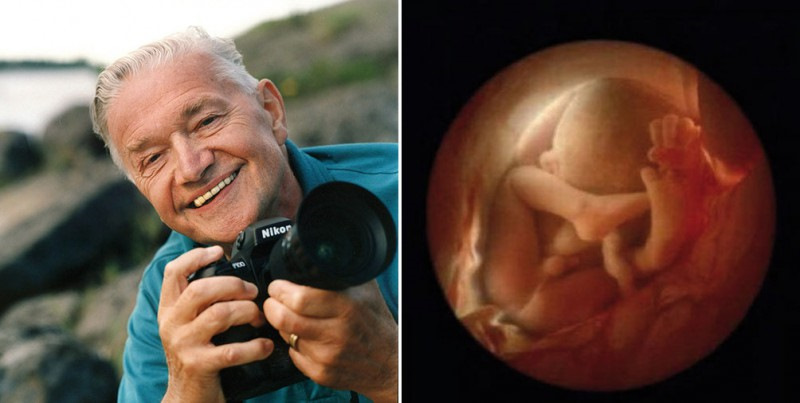

Зарождение жизни: Фотографии Леннарта Нильсона